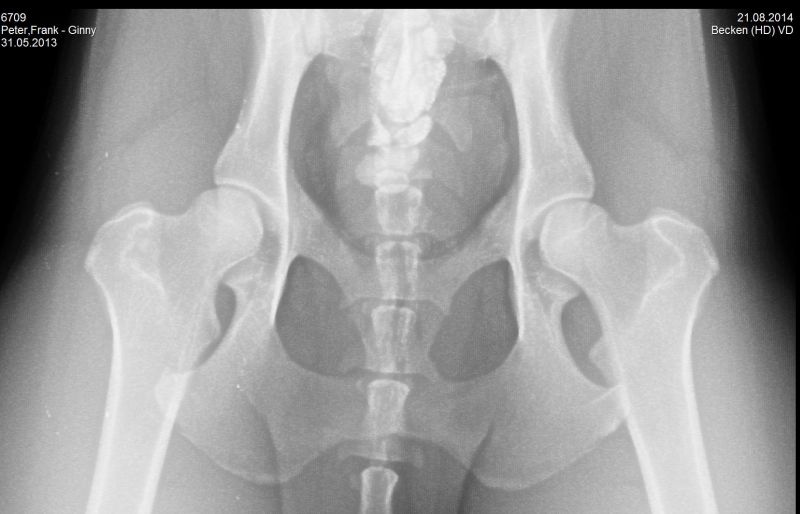

21.08.2014 - Ginny HD-und ED geröntgt - 15 Monate alt

24.08.2014 - Ginny - 15 Monate alt